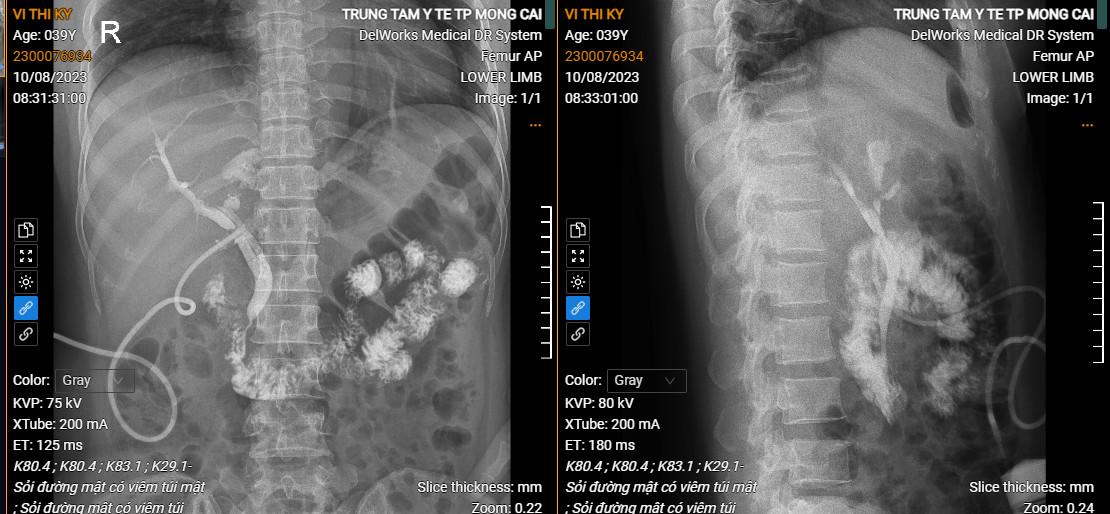

Hình ảnh sỏi đường mật có viêm túi mật do TTYT cung cấp

Trước kia, đối các bệnh lý sỏi mật vẫn là thách thức với các Bác sĩ Ngoại khoa tuyến cơ sở. Tuy nhiên, trong những năm gần đây, xác định rõ công tác chăm sóc sức khỏe ban đầu cho nhân dân là nhiệm quan trọng hàng đầu của đội ngũ cán bộ viên chức y tế, TTYT Thành phố Móng Cái đã tập trung nâng cao chuyên môn và triển khai rất nhiều kỹ thuật kinh điển như: mổ nội soi lấy sỏi ÔMC, dẫn lưu kerh, cắt túi mật đối với sỏi ống mật chủ viêm túi mật; mổ cắt thùy gan trái lấy sỏi trong gan trái, mở ống mật chủ dẫn lưu kerh; mổ nội soi cắt túi mật với những bệnh nhân sỏi túi mật biến chứng viêm hoại tử túi mật, viêm tụy cấp…